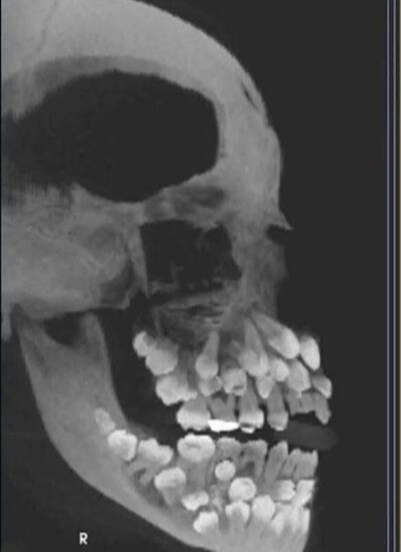

本來以為就是個簡單的拔牙小事,結果 X 光片一出來,大家都傻眼了 —— 這個 11 歲的小女童女童嘴裡居然塞著 81 顆牙!

可這、小女童倒好,18 顆乳牙賴著不走,32 顆恆牙按時報到,還額外冒出 30 多顆「不速之客」,也就是醫生說的「多生牙」。這些額外的牙齒擠在嘴裡,簡直像在搞「牙齒大聯歡」。